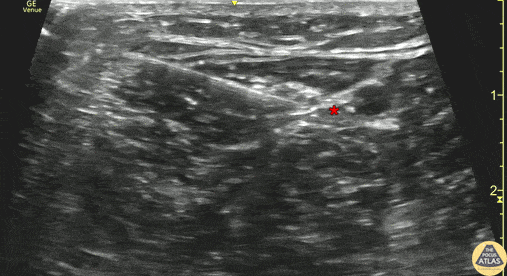

30s M presented with foot pain after his foot was run over by a car while he was riding a moped. He had lacerations over the plantar aspect of his foot without underlying fracture on XR. To facilitate wound irrigation and dressing, a posterior tibial nerve block was performed. The block is shown here, with the medial malleolus just out of view to the right of the image. The needle approaches in plane from the posterior aspect, and deposits anesthetic adjacent to the posterior tibial nerve (*). The posterior tibial artery is seen pulsating just anterior (right of screen) to the nerve. The patient had anesthesia achieved and his wounds were able to be irrigated and dressed. Dr. Carleigh Benton, PGY-4 Denver Health Residency in Emergency Medicine